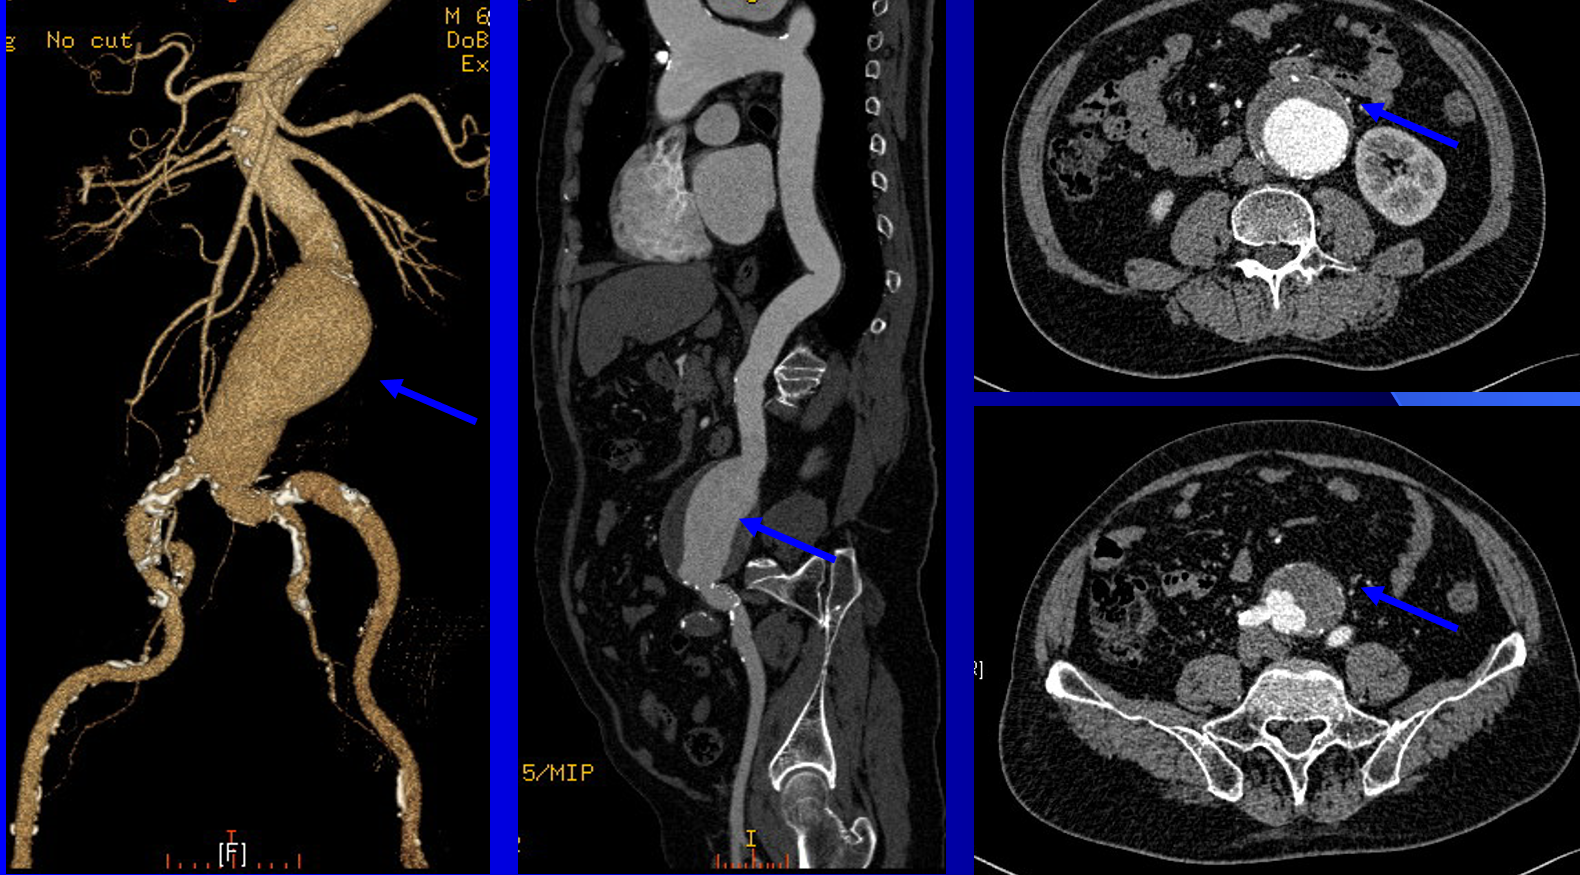

搏动性肿物:颈部、肢体或腹部摸到搏动性肿物,搏动频率与心跳相近,提示可能存在动脉瘤,如不及时治疗甚至会破裂危及生命。